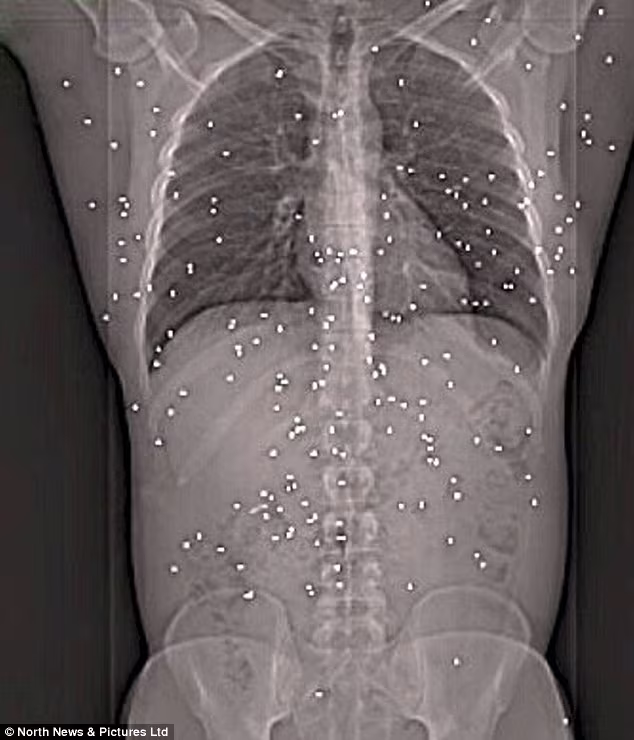

Qua kết quả chụp x-quang, các bác sỹ phát hiện có 150 viên đạn trong cơ thể của Joe Clark

Ngay sau đó, anh được đưa tới bệnh viên cấp cứu, các bác sỹ tại đây đã chụp x-quang và phát hiện thấy có 150 viên đạn găm vào người của anh. Tuy nhiên, một số viên đạn đã không được lấy khỏi cơ thể anh bởi chúng dính vào bộ phận quan trọng.